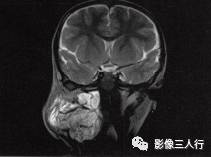

A.B.MRI T1WI显示右侧上颈部大片混杂低信号,其内见蜂窝状更低信号,肌间隙显示不清,并见点、线状高信号。咽、喉、气管受压移位;C〜F.T2WI的横断面、冠状面病变表现为不均匀高信号,形态不规则,可见病变向上、下,向左、右延伸,有“见缝就钻”的特点,气管及周围软组织受压移位

2)MRI在冠状面、矢状面可显示病灶向上下、左右浸润的范围,具有“见缝就钻”的特点。

3.T2WI病变表现为不均匀的高信号,形态不规则,其内可见分隔,具有“见缝就钻”的特点。气管及周围软组织受压移位。